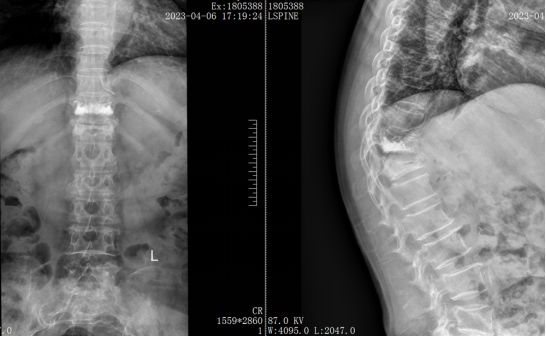

在经历了多次求医未果后,老人被转诊至漯河市中心医院脊柱外科。在这里,专家团队进行了详细的评估和反复讨论。患者被诊断为重度骨质疏松症、胸11~12椎体压缩骨折、胸11椎体PVP术后,脊柱角状后凸畸形、胸椎管狭窄症、心肺功能不全等多种疾病。针对高龄且多种并发症的复杂病情,如何在保障患者安全的前提下解除痛苦,成为了摆在医生面前的一道难题。

面对挑战,脊柱外科的专家们迎难而上。他们决定采用O臂机导航技术精准置入椎弓根螺钉、采用骨水泥螺钉加固技术提高螺钉的牢固性,并应用超声刮匙行PSO截骨术,以实现微创的减压、矫形。这是一种复杂而精细的手术方式,尤其适用于高龄且伴有心肺功能不全的患者。为了确保手术成功,医护团队对每一个细节都做了精心准备,制定了周密的手术方案。